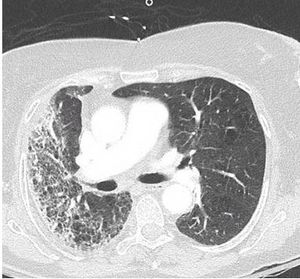

Two weeks after injury to the right chest wall and shoulder, the patient continues to have pain. He also reports numbness and tingling in his hands bilaterally. What do the ED images reveal?

Results of a physical examination and CT scan of the chest offer clues to this patient's diagnosis.